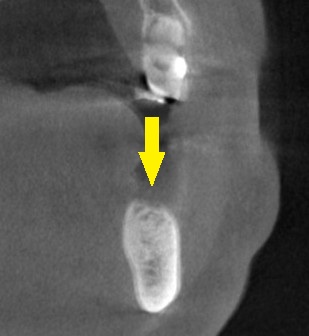

下の写真3段目が手術後のCTです。

インプラントと神経までの距離は確保され、インプラント上方は人工骨で覆われています。